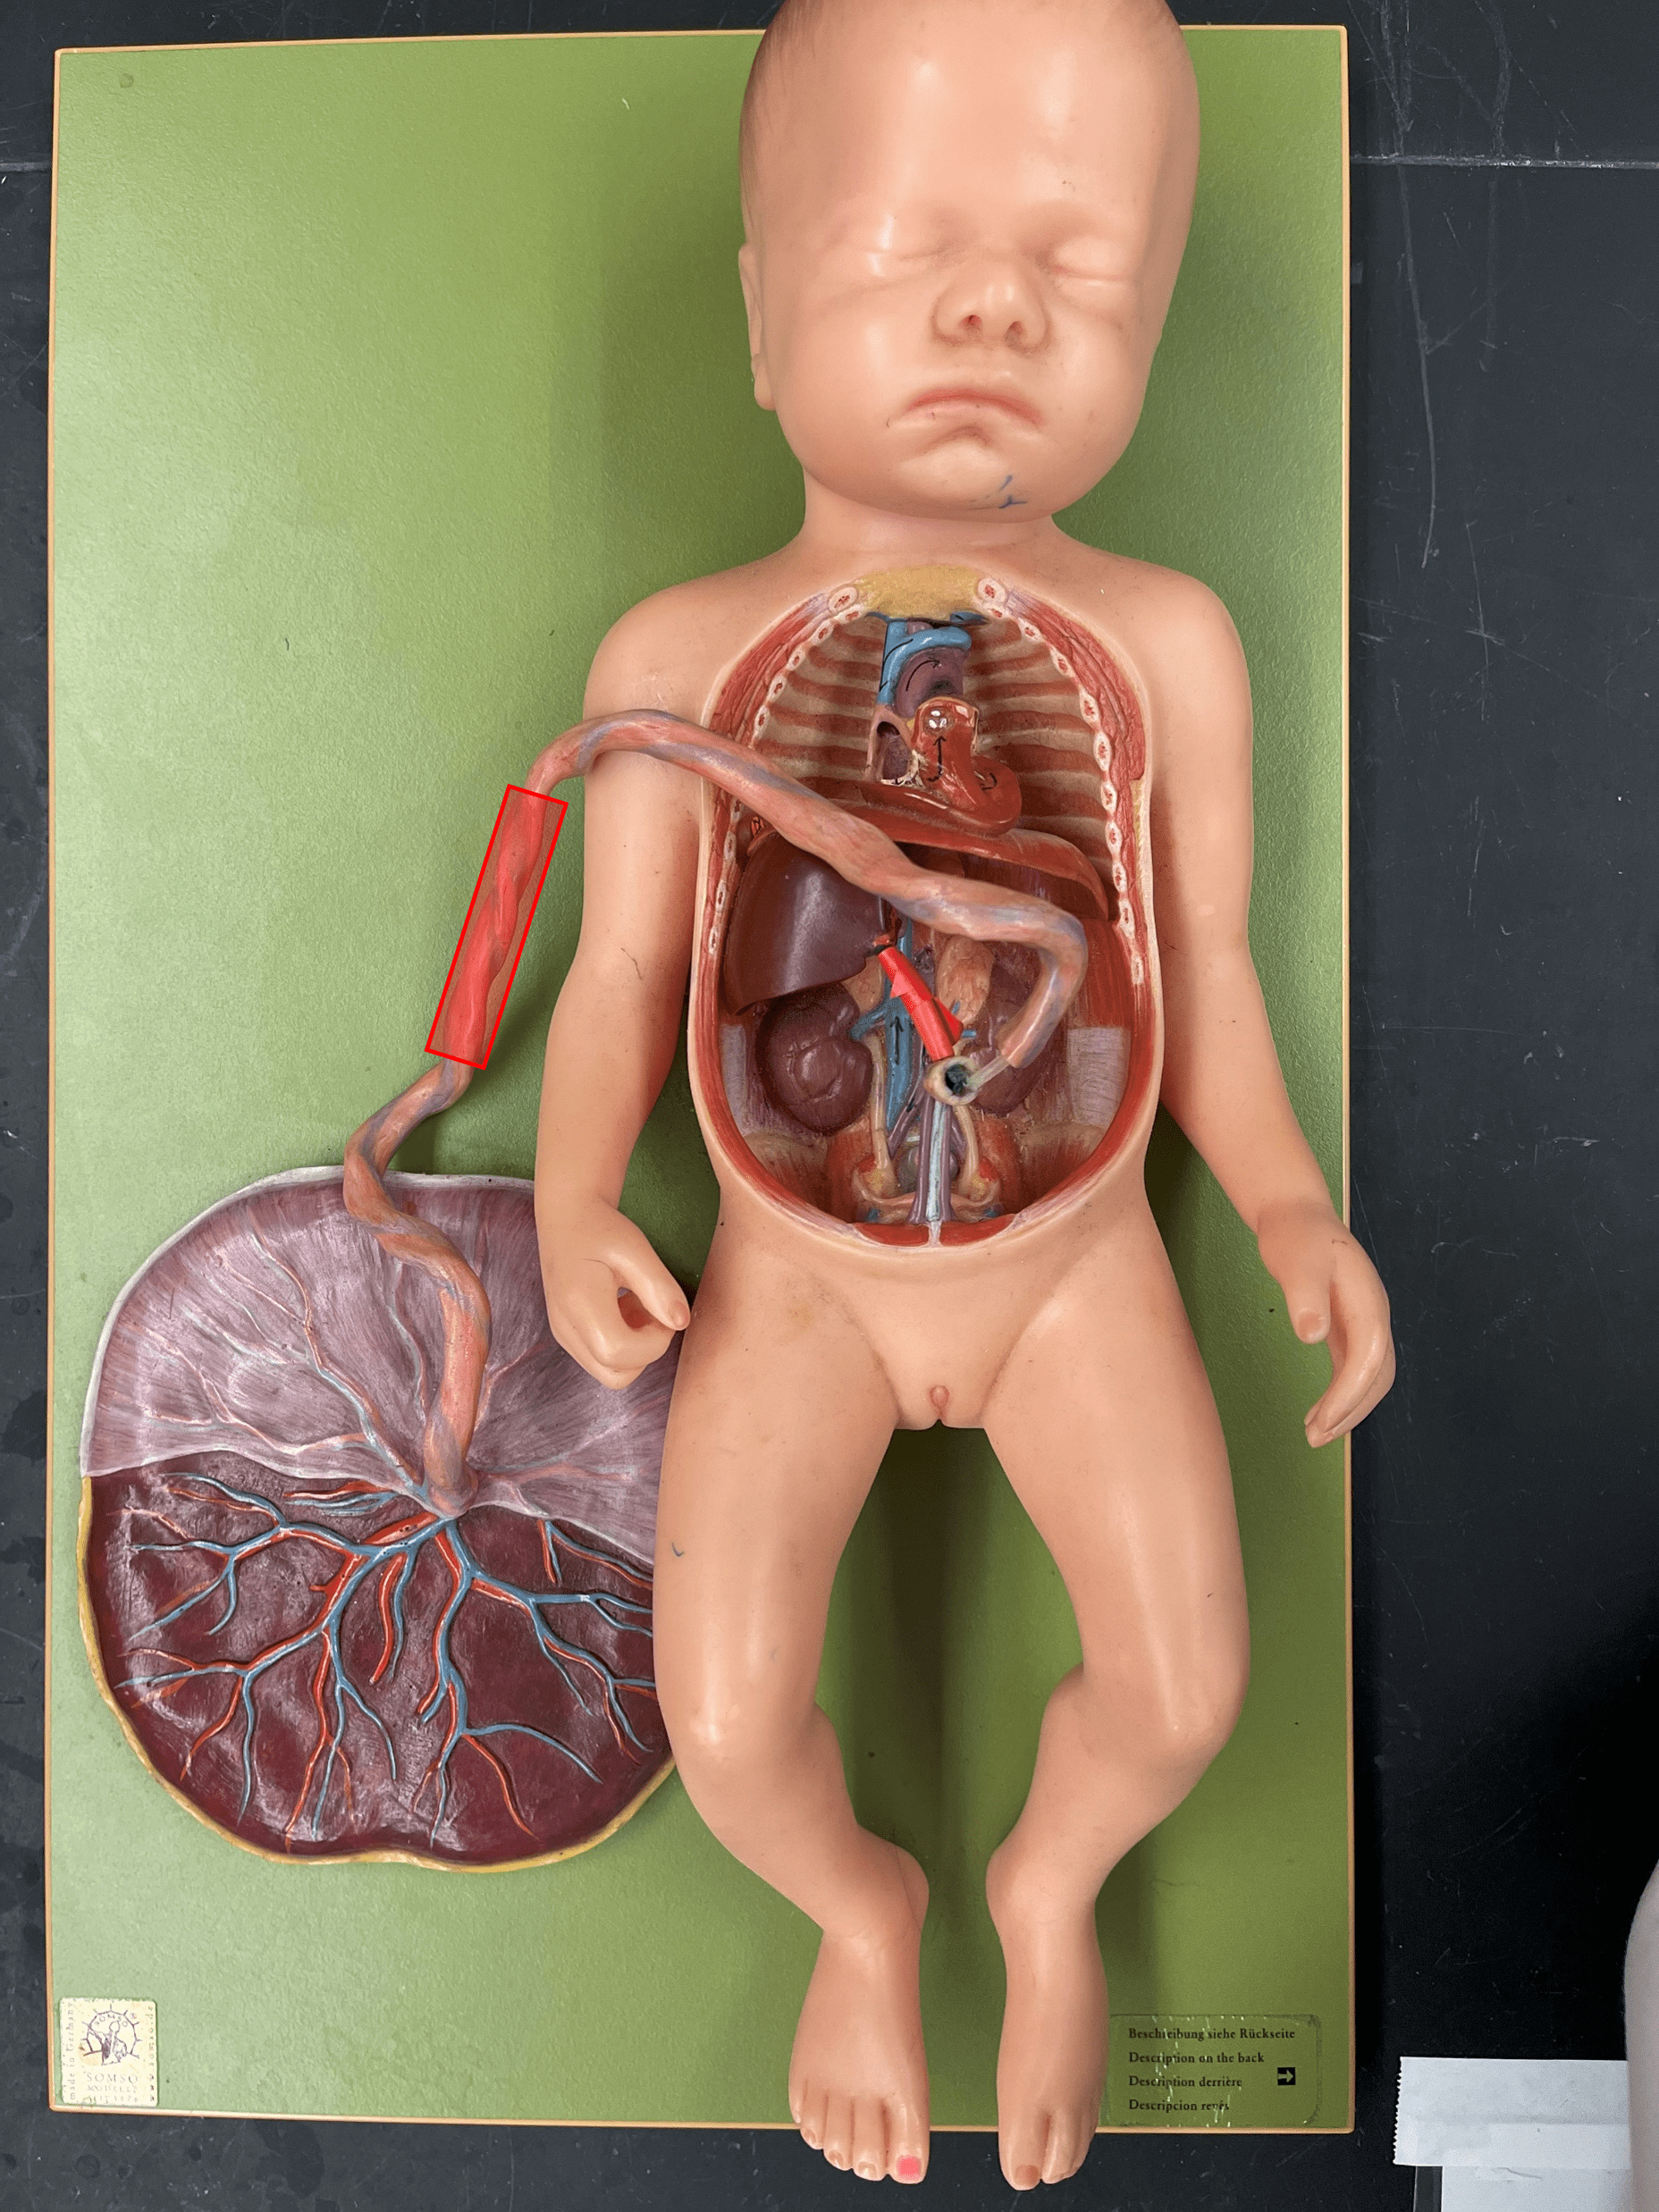

umbilical cord

• Connects the fetus to the placenta.

• Contains an umbilical v. and two umbilical aa. as part of the fetal circulation.

• Contains an umbilical v. and two umbilical aa. as part of the fetal circulation.

ductus venosus

• Part of the fetal circulation.

• Shortcuts blood to the inferior vena cava, bypassing the liver.

• Becomes the ligamentum venosum.

• Shortcuts blood to the inferior vena cava, bypassing the liver.

• Becomes the ligamentum venosum.